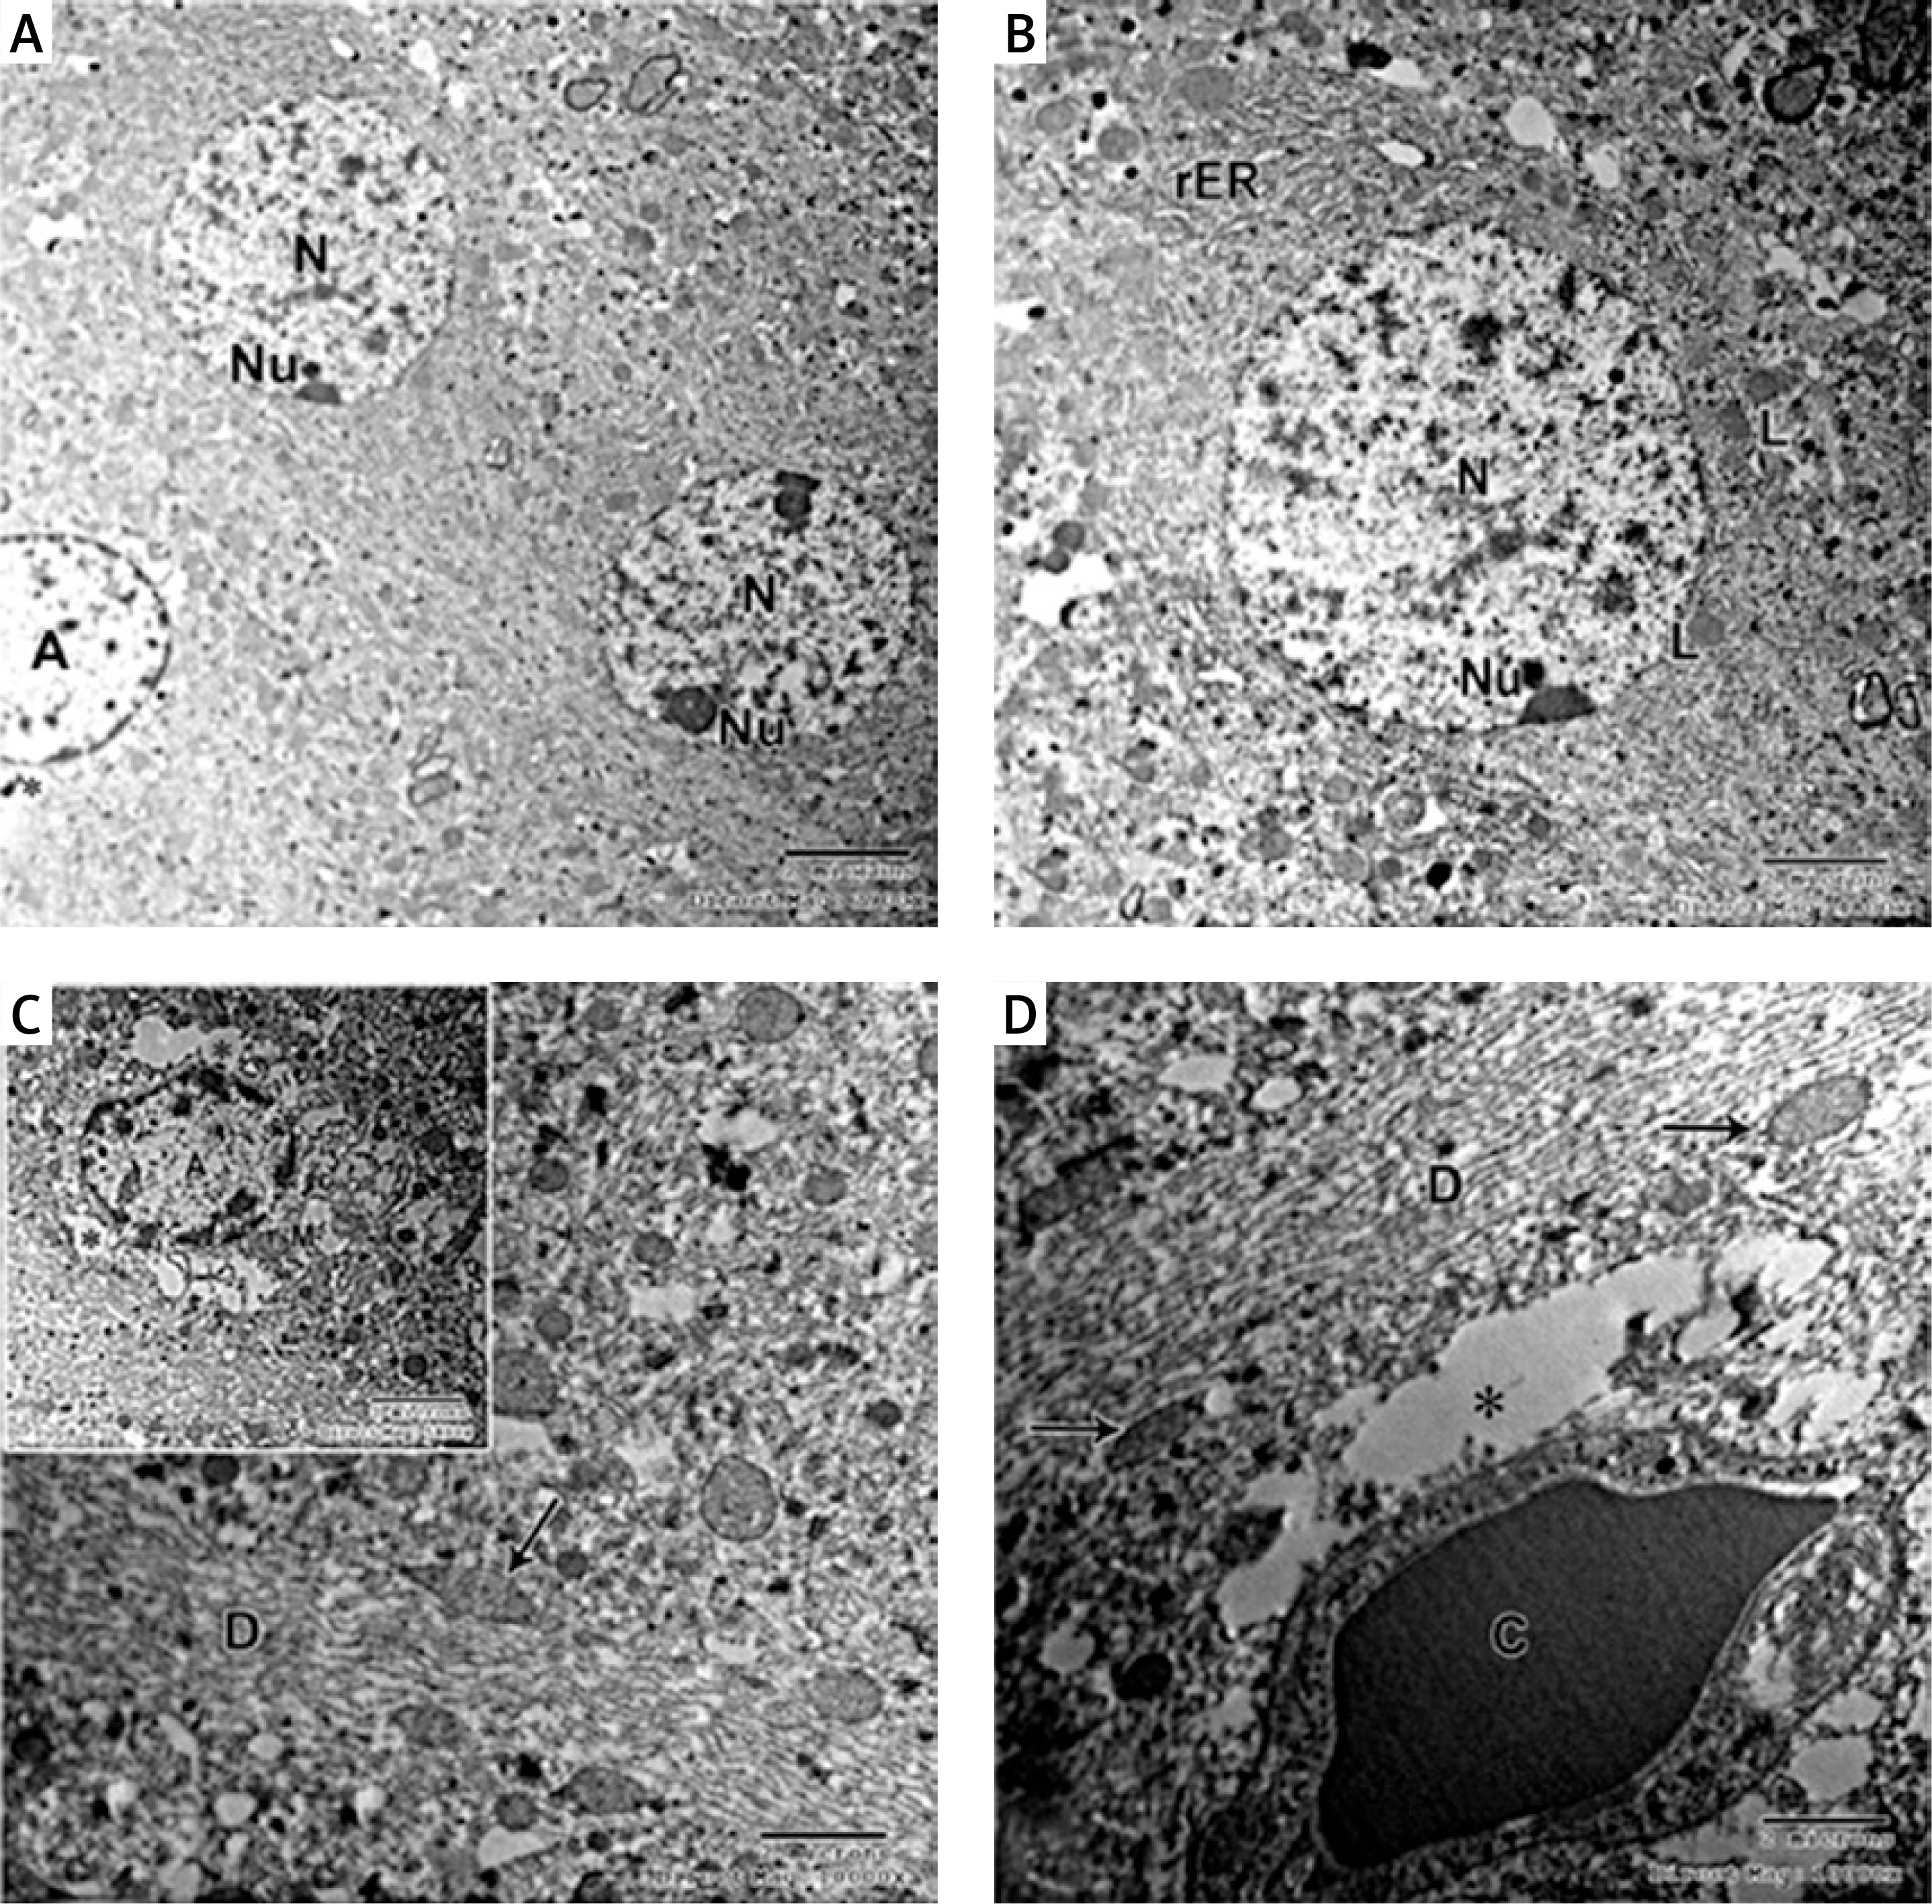

Electron microscopy

Electron micrograph of the control CA1 field showed pyramidal neurons which were uniform in size with large rounded euchromatic nuclei with finely dispersed chromatin and prominent nucleoli. The surrounding cytoplasm contained numerous rough endoplasmic reticulum, free ribosomes and few lysosomes (Figures 6 A, B, D). A large dendrite containing microtubules and mitochondria was present (Figure 6 C). The astrocyte had a large oval euchromatic nucleus and intact mitochondria (Figure 6 D). A blood capillary with a wide lumen lined with endothelial cells and surrounded by pericytes was also observed (Figure 6 C).

Figure 6

A – Electron micrograph of the control group CA1 field showing numerous pyramidal neurons with euchromatic nuclei (N) and prominent nucleoli (Nu). Scale bar 2 µm and direct magnification 2900. B – A magnified part of control CA1 field showing the pyramidal neurons with euchromatic nuclei (N), prominent nucleolus (Nu), and numerous rough endoplasmic reticulum (rER). Scale bar 2 µm and direct magnification 4800. C– Electron micrograph of the control CA1 field showing dendrite (D) with well-organized microtubules and oval mitochondria (M). Scale bar 2 µm direct and magnification 10000. The inset shows blood capillary with wide lumen surrounded by pericyte (P). Scale bar 2 µm direct and magnification 5800. D – Electron micrograph of the control group CA1 field showing astrocyte (A) with large rounded nucleus, the cytoplasm surrounds the nucleus with short strands of rER and mitochondria (M). Neurons with extensive rER and small lysosome-like dense bodies (L) are present. Scale bar 2 µm and direct magnification 4800

In the APAP-E group, the CA1 field showed irregular electron-dense degenerating pyramidal neurons with ill-defined nuclei scattered among normal electron-lucent neurons, which had euchromatic nuclei and prominent nucleoli (Figure 7 A). These dark neurons were surrounded by dilated astrocytic processes (Figure 7 A). The cytoplasm exhibited swollen mitochondria with an electron-lucent matrix containing few cristae (Figure 7 B). Numerous large lysosome-like dense-bodies were present (Figures 7 B, C). Some dendrites were dark, while others were light-stained and revealed mitochondria as multiple individual teardrop-shaped organelles connected by thin membrane or mitochondria-on-a-string (MOAS) (Figures 7 A, D).

Figure 7

A – Electron micrograph of autophagy protects against acetaminophen induced encephalopathy group (APAP-E ) CA1 field showing electron dense irregular pyramidal neurons (thick arrow) with ill-defined nuclei and dark dendrite (arrowhead) among normal electron lucent neurons (N). Note the dilated astrocytic processes (*) surrounding the dark neurons and small blood capillary (C). Scale bar 2 µm and direct magnification 2900. B – Electron micrograph of CA1field of APAP-E group showing part of neuron (N) containing swollen mitochondria (M) with electron lucent matrix containing a few cristae. Note the presence of numerous lysosomes (L). The arrow points to part of dark neuron with ill-defined nucleus. Scale bar 2 µm and direct magnification 10000. C – Electron micrograph of APAP-E group CA1 field showing part of neuron with large irregular euchromatic nucleus (N) and numerous lysosomes (L). Scale bar 2 µm and direct magnification 10000. D – Electron micrograph of APAP-E group CA1 field showing a dendrite (D) with elongated pointed end mitochondria (M) interconnected by thin membranes (arrow) the inset showing interconnected mitochondria and mitochondria with long process. Scale bar 2 µm and direct magnification 7200. E – Electron micrograph of CA1field of APAP-E showing astrocyte prominent thick electron lucent processes (*). Note the presence of numerous dense bodies (arrow). Scale bar 2 µm and direct magnification 5800

The astrocyte appeared with a heterochromatic nucleus having a prominent thick electron lucent processes surrounding the dark neurons and small blood capillary (Figures 7 A, E).

As regards the CoQ10-treated group, the pyramidal neurons appeared with large euchromatic nuclei and prominent nucleoli. The cytoplasm appeared translucent with several intact mitochondria and a huge amount of rER and large lysosome (Figures 8 A–C). The dendrite appeared normal, with well-organized microtubules and mitochondria (Figures 8 C, D). The astrocyte appeared with a rounded large euchromatic nucleus and prominent nucleolus. Its cytoplasm had short strands of rER and intact mitochondria (Figure 8 E).

Figure 8

A – Electron micrograph of CA1 field of coenzyme Q10-treated (CoQ10-treated) group showing multiple normal shaped pyramidal neurons with euchromatic nuclei (N). The cytoplasm has lysosome-like dense bodies (L). Scale bar 2 µm and direct magnification 2900. B – Electron micrograph of CA1field of CoQ10-treated group showing large electron lucent pyramidal neuron (N) and prominent nucleolus (Nu); its cytoplasm has several intact mitochondria (M) and a huge amount of rough endoplasmic reticulum (rER). Scale bar 2 µm and direct magnification 4800. C – Another pyramidal neuron with euchromatic nucleus (N) and prominent nucleolus (Nu), numerous rER and large lysosome (L). Astrocyte (A) with heterochromatin clumps is present. Scale bar 2 µm and direct magnification 4800. D – A magnified part of the previous micrograph showing part of the neuron with large lysosome (L) and normal mitochondria (M). Note the dendrite (D) with organized microtubules. Scale bar 2 µm and direct magnification 7200. E – Electron micrograph of CA1field of CoQ10-treated group showing astrocyte with euchromatic nucleus (N), prominent nucleolus (Nu), numerous short strands of rER and intact mitochondria (M). Scale bar 2 µm and direct magnification 5800